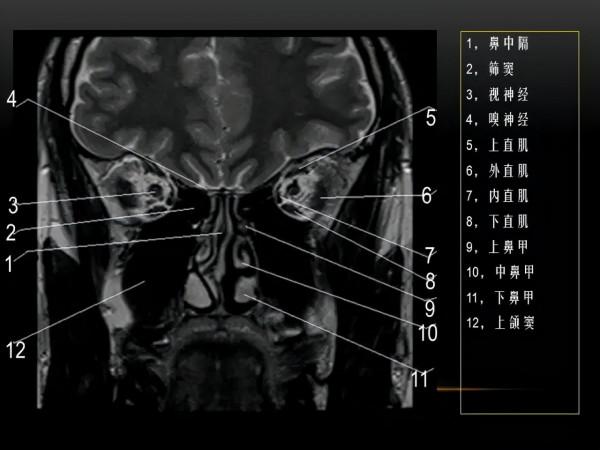

MRI下眼部及鼻竇的冠狀位解剖